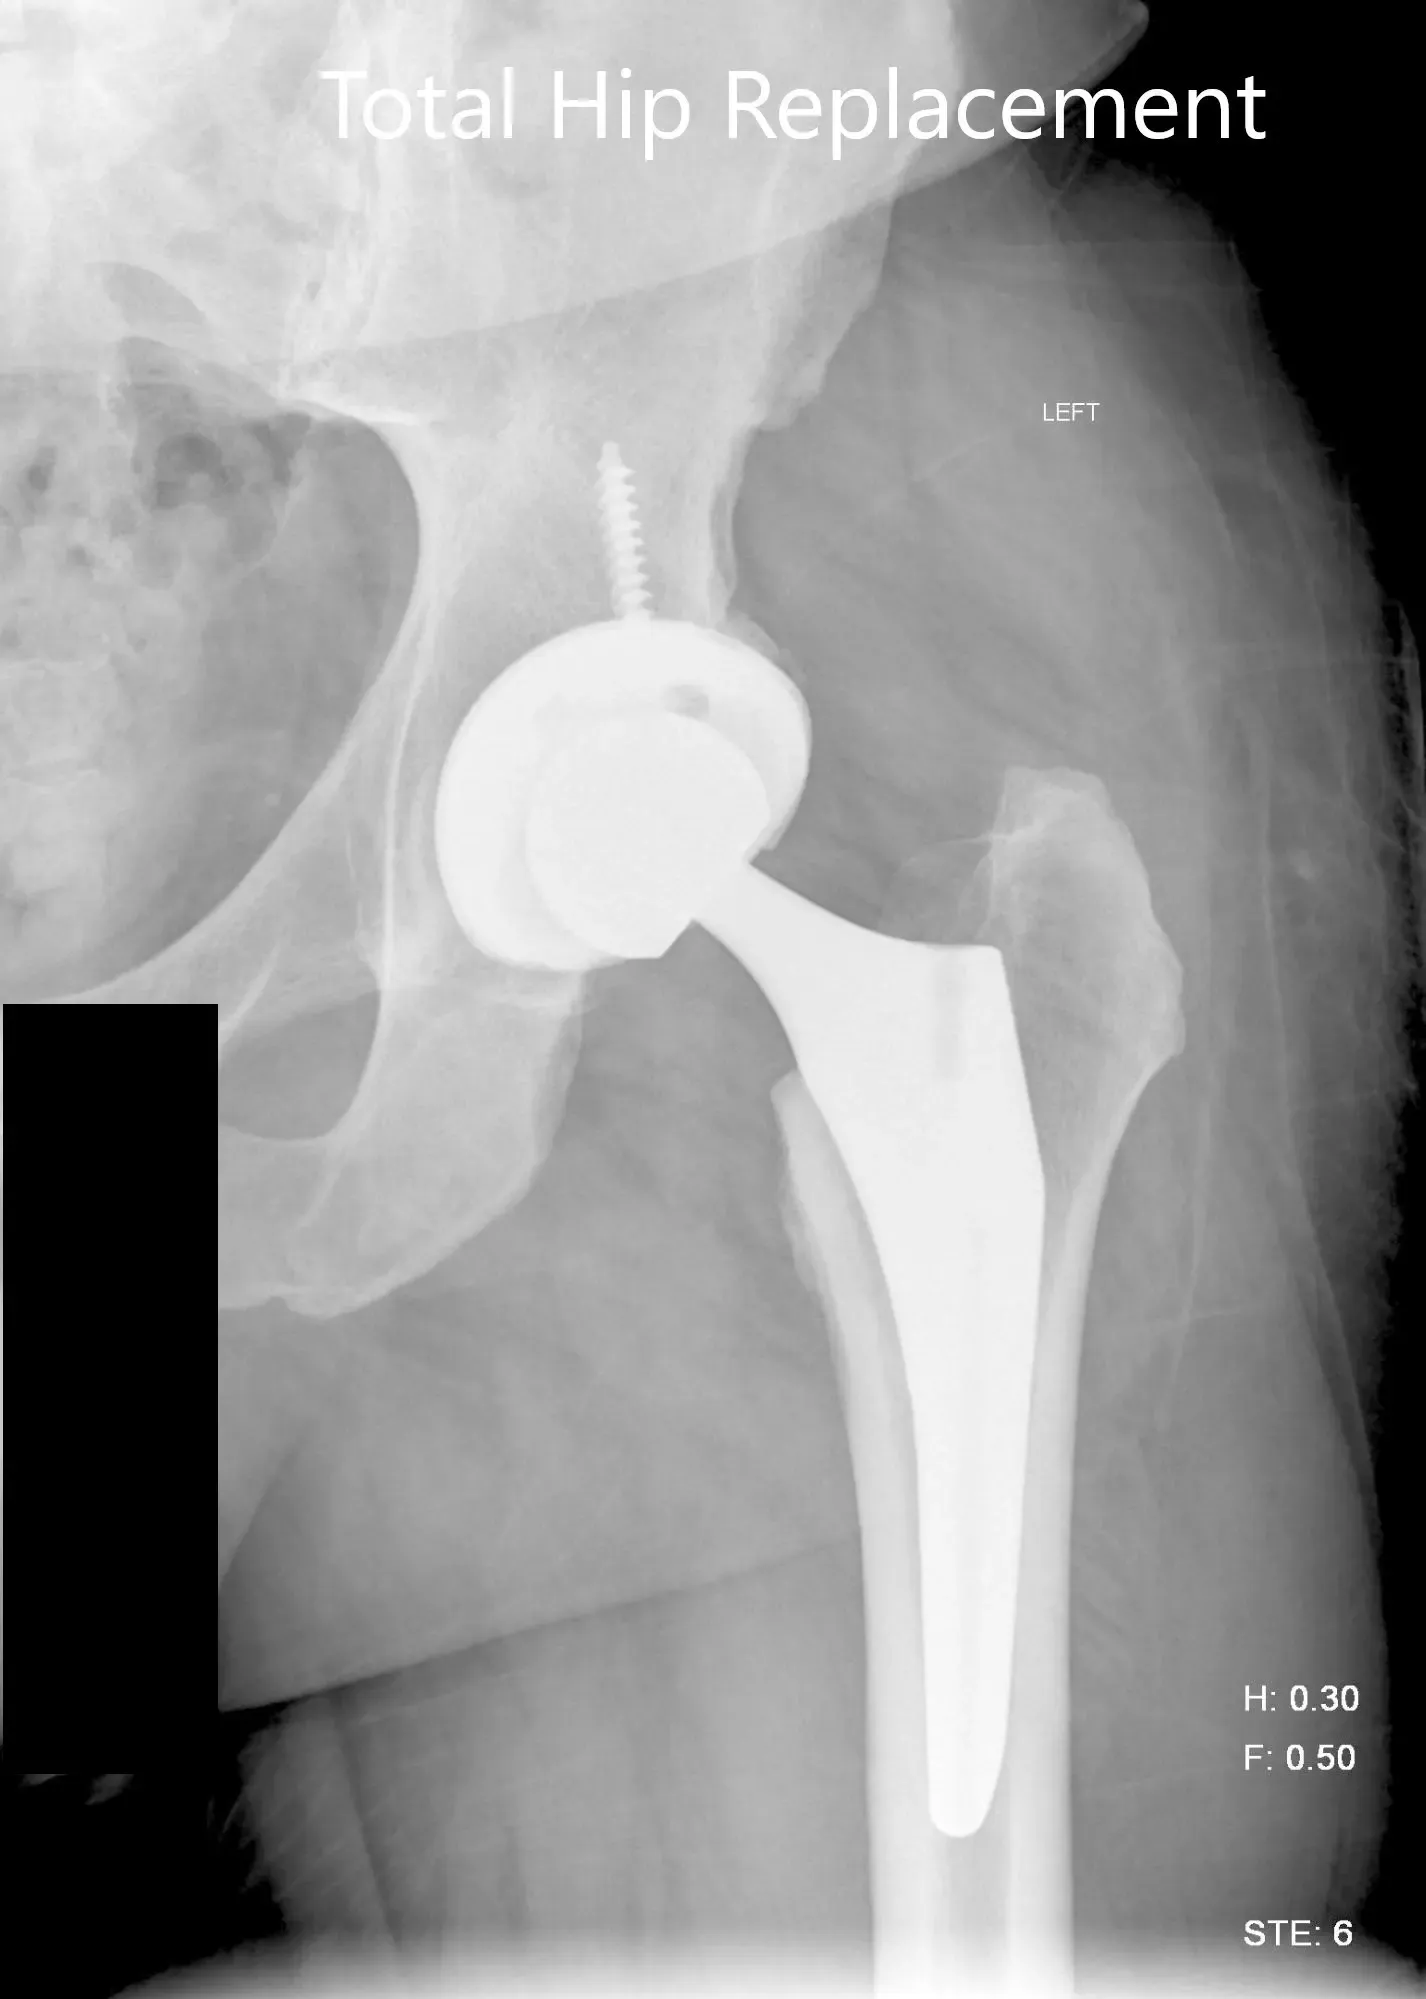

Imágenes de radiografías postoperatorias que muestran la vista AP y la vista lateral con patas de rana.